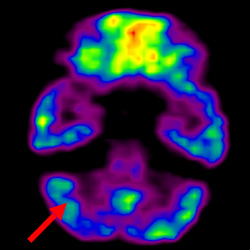

細胞治療后,藍色和黑色區域減少,并且看到更活躍的區域。這表明損傷減少并改善了大腦功能。

細胞治療前 PET CT 掃描顯示神經組織中的藍/黑色區域,表明腦癱引起的大腦損傷。

這證明細胞療法是治療腦癱兒童安全有效的方法。細胞療法可以更新大腦損傷的核心,并且可以通過 PET CT 掃描來監測大腦的改善情況。這些細胞療法與標準治療一起促進腦癱兒童的生長和改善。